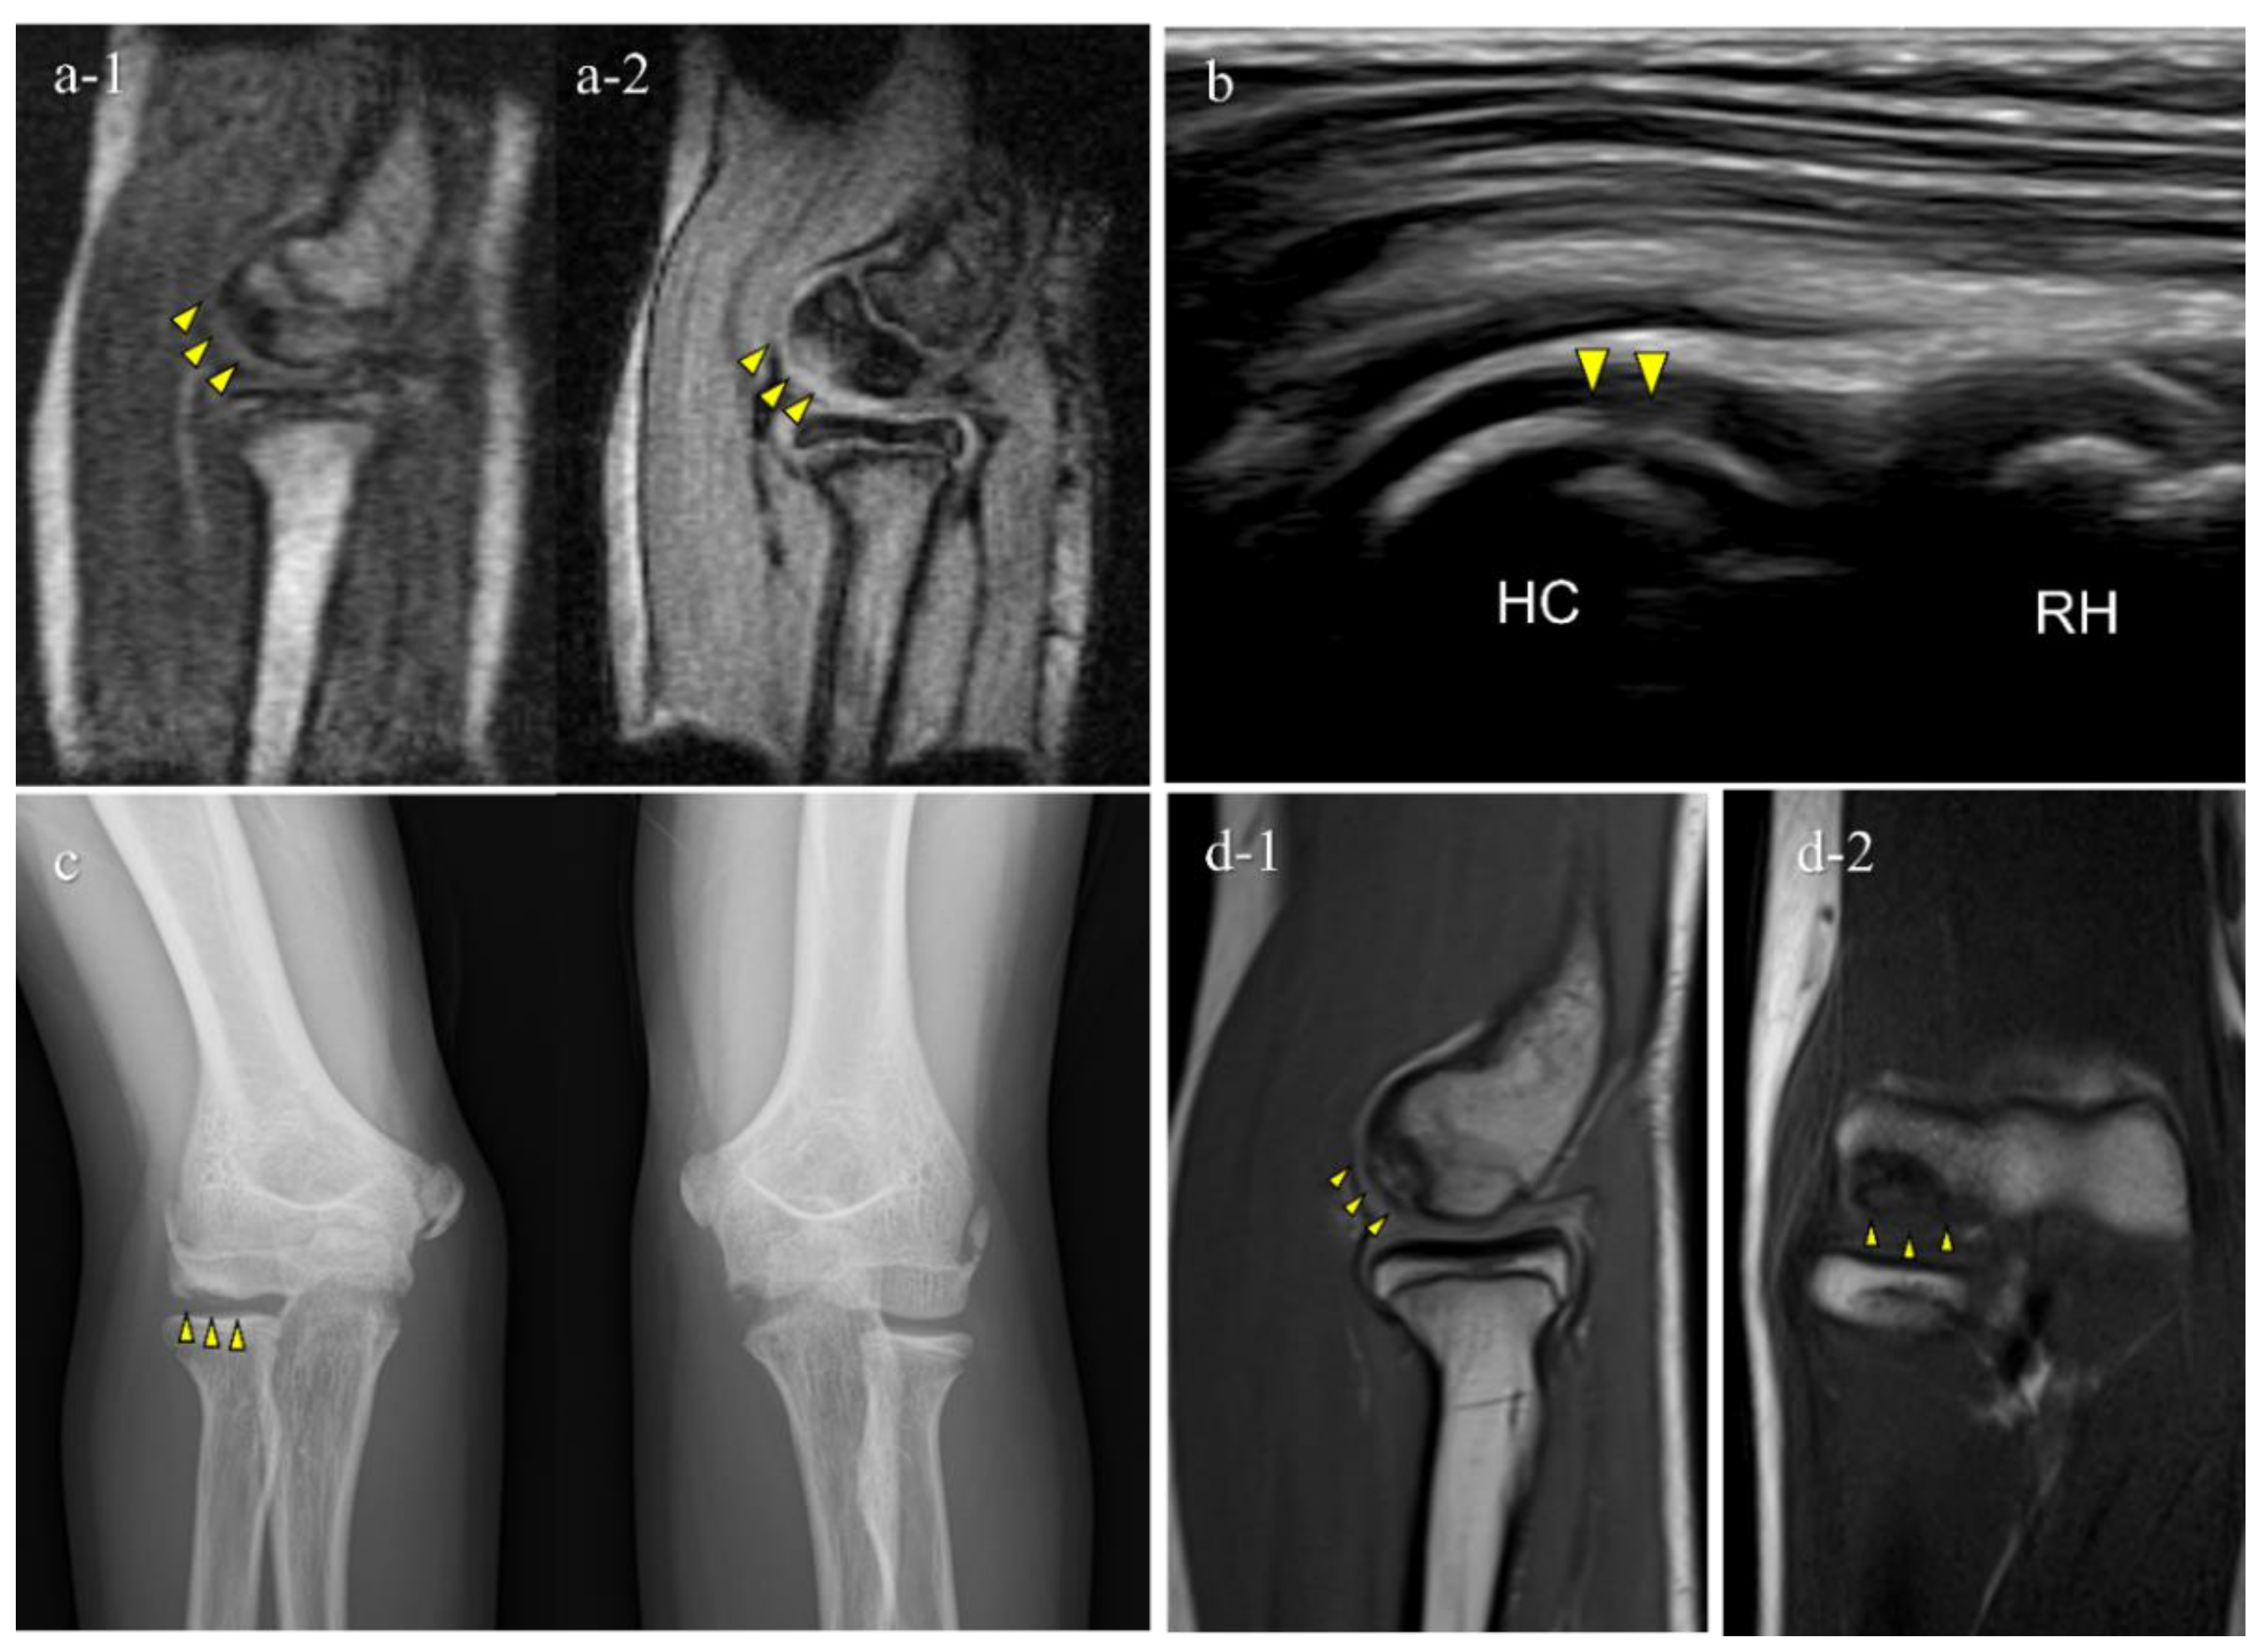

| 1 | 12 | M | - | − (1st) | + (B) | OCD | II | lateral | 15 |

| 2 | 11 | M | + | + (1st) | + (B) | OCD | I | central | 10 |

| 3 | 12 | M | - | + (2nd) | + (B) | OCD | II | central | 9 |

| 4 | 12 | M | + | + (2nd) | + (B) | OCD | II | lateral | 11 |

| 5 | 12 | M | + | + (2nd) | − (B) | OCD | I | central | 3.5 |

| 6 | 15 | F | - | + (2nd) | − (C) | not OCD | posterior | 3.5 | |

| 7 | 12 | M | - | + (2nd) | − (D) | OCD | I | central | 5.5 |